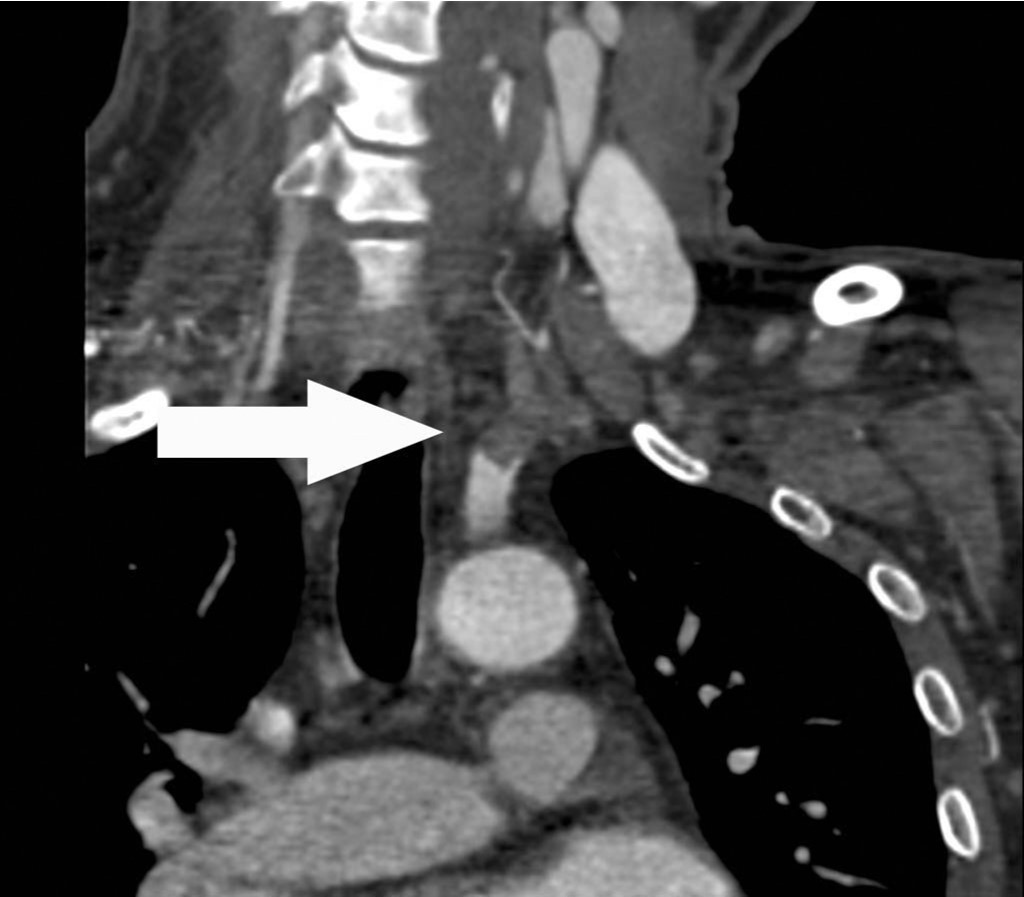

상지 CT 혈관조영술 관상면 영상에서 좌측 쇄골하동맥의 근위부에서 약 7cm에 걸쳐 혈전색전증에 의한 혈관의 부분폐쇄가 확인되고(Fig. 1A, B, C), 혈전색전증은 좌측 추골동맥 근위부로도 연장되어 있음(Fig. 1D).

Fig. 1. A-D

Fig. 1A-D Coronal CT images show a partial thrombotic occlusion at proximal subclavian artery (SCA, arrow in Fig. 1A-C), and proximal vertebral artery (VA, arrow head in Fig. 1D).